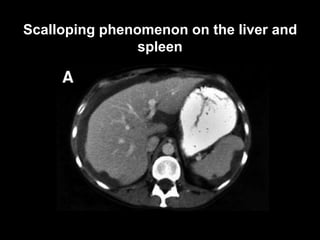

CT

Scalloping phenomenon on the liver and

spleen

• the medical imaging is fundamental in the diagnosis and

the surveillance of this rare pathology. US permits a

better characterization of the ascites whereas the CT

visualizes the calcifications and the scalloping effect.